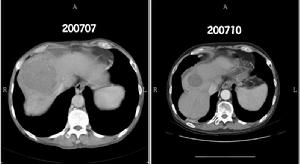

3.CT表現:平掃可見腎局部隆起,內部密度不均勻偏低,其內可見斑片或小點狀鈣化,有時呈蛋殼狀;增強掃描後正常部分腎增強明顯,而癌內增強較低,內部增強程度不規則,有更低密度的壞死區存在。癌可穿破包膜進入腎周脂肪層,晚期穿破腎筋膜擴散至腎外組織。腎細胞癌分期多採用Robson分期法,即Ⅰ期癌限於腎包膜內;Ⅱ期癌已穿破包膜,侵入脂肪層,仍局限在腎筋膜內;Ⅲ期癌已侵入腎靜脈或(和)下腔靜脈,局部淋巴結可能有轉移;Ⅳ期癌已穿破腎筋膜,侵入鄰近臟器或發生遠處轉移。